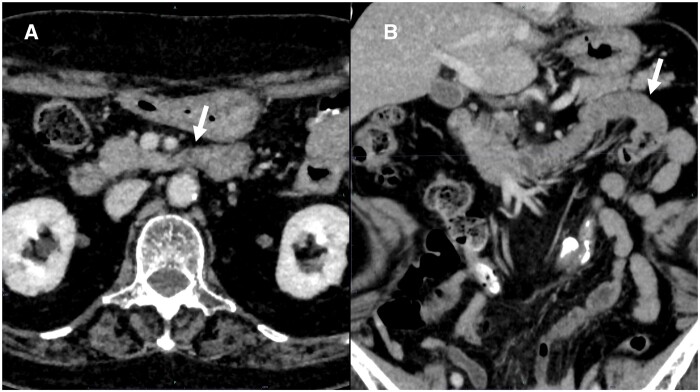

A 77-year-old woman underwent CT to evaluate haematemesis. The images showed that the third part of the duodenum flexed steeply on the right side of the aorta and ran caudally, without crossing anterior to the aorta. The duodenal-jejunal junction and jejunum were located on the patient's right side. Upper gastrointestinal endoscopy revealed a laceration at the gastric cardia, and a diagnosis of Mallory-Weiss syndrome was made. Repeat CT 7 days later revealed that the abnormal positioning of the intestinal tract had resolved spontaneously. Two months later, the patient experienced another episode of haematemesis, and CT revealed repeat deviation of the duodenal-jejunal junction and jejunum to her right side. Upper gastrointestinal endoscopy revealed another laceration at the gastric cardia, as in the previous study. On the basis of the initial CT findings showing the duodenal-jejunal junction in the right hemi-abdomen, intestinal malrotation was suspected. However, because the jejunum deviated repeatedly to the right side but resolved spontaneously, we diagnosed dysplasia of the ligament of Treitz. Laparotomy revealed a formed ligament of Treitz; however, fixation in the upper jejunum was incomplete. Additionally, CT revealed that the anterior pararenal space was loosely fixed and mobile. These factors may have caused the right-sided deviation of the small intestine. In this case, the third part of the duodenum likely flexed on the right side of the aorta, causing an obstruction that resulted in repeat vomiting episodes and Mallory-Weiss syndrome.

一位77岁的女性接受了CT检查以评估呕血情况。图像显示十二指肠第三段在主动脉右侧急剧弯曲并向尾侧延伸,未穿过主动脉前方。十二指肠-空肠交界及空肠位于患者右侧。上消化道内窥镜检查显示贲门处有撕裂伤,诊断为Mallory-Weiss综合征。7天后复查CT显示肠道定位异常自行消退。2个月后,患者再次出现呕血,CT显示十二指肠-空肠交界处和空肠再次向右侧偏移。上消化道内窥镜检查显示贲门处有另一个撕裂伤,与先前的研究相同。根据最初的CT表现显示十二指肠和空肠交界在右半腹部,怀疑肠旋转不良。然而,由于空肠反复向右偏但自行消退,我们诊断为Treitz韧带发育不良。剖腹探查发现形成的Treitz韧带;然而,上空肠的固定是不完整的。此外,CT显示肾旁前间隙松散固定并可移动。这些因素可能导致小肠向右偏移。本例中,十二指肠第三部分可能在主动脉右侧屈曲,造成阻塞,导致反复呕吐和Mallory-Weiss综合征。